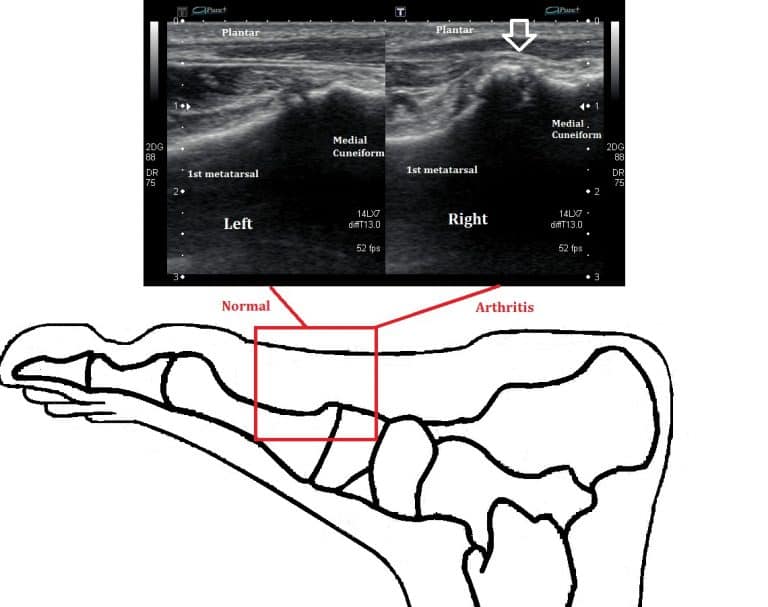

At the Ankle, Foot and Orthotic Centre we are able to provide additional information about the presence of midfoot arthritis with ultrasound imaging. Typically there will be sclerosis of the midfoot joints and a loss of articular cartilage.

Moderate arthritis of the joint of the navicular and medial cuneiform

Normal left foot